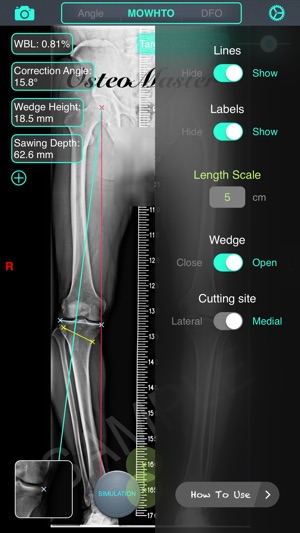

‎截骨神器 - 用于高胫骨截骨术(HTO)和股骨远端截骨术(DFO)的手术前术前规划工具。 特征: 1. 测量骨骼的解剖或力学軸角度,只需通过相机或照片库输入图像。 2. 计算术前负重线(WBL)和规划目标WBL。 3. 自动计算截骨矫正角度、楔块高度、切锯深度与脚长变化。 4. 设定期望WBL,矫正角度,缺口高度,MPTA或LDFA 5. 提供開放(open)或閉合(close)、内侧(medial)或外侧(lateral)截骨。 6. 模拟截骨调整后结果。 教学視頻:https://v.qq.com/x/page/h0527kc4vj1.html 簡体用户指南:http://pan.ba…